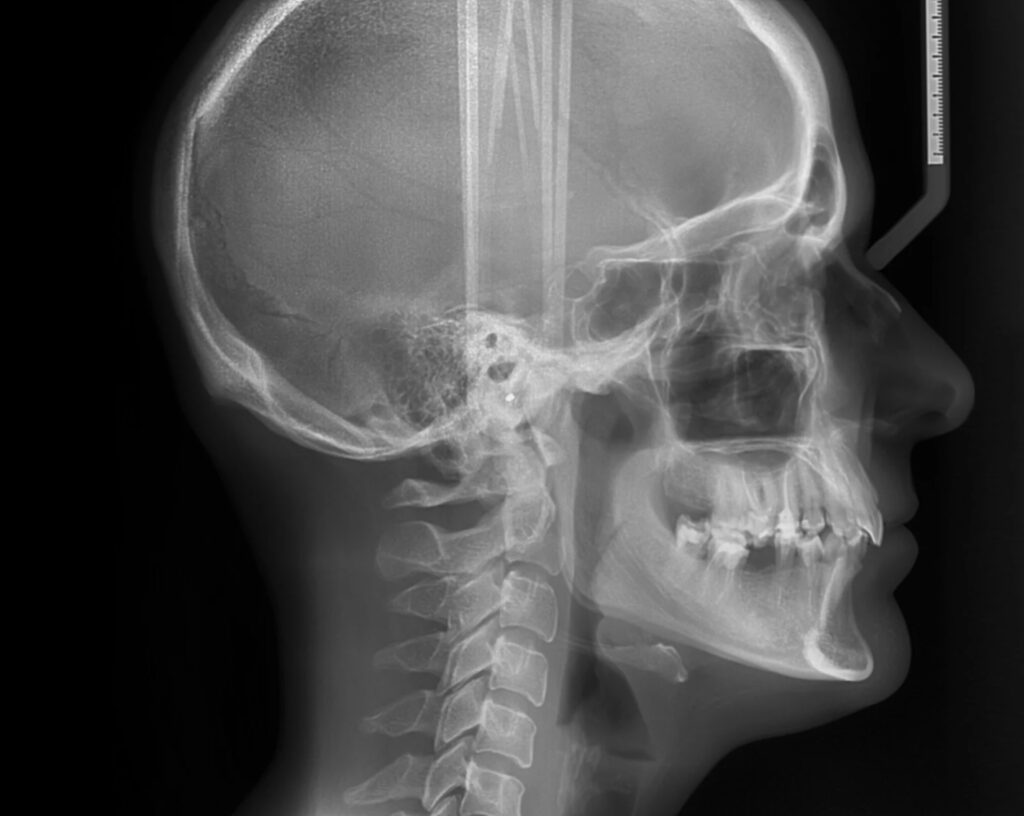

① セファロ分析(頭部X線規格写真)

矯正治療では、

- セファロ(側面規格X線)

- 顔貌写真

を用いて、

- 歯の位置

- 顎の骨格

- 唇と鼻のバランス

を数値と形の両方で分析します。

ナゾラビアル角も、この分析の中で確認します。